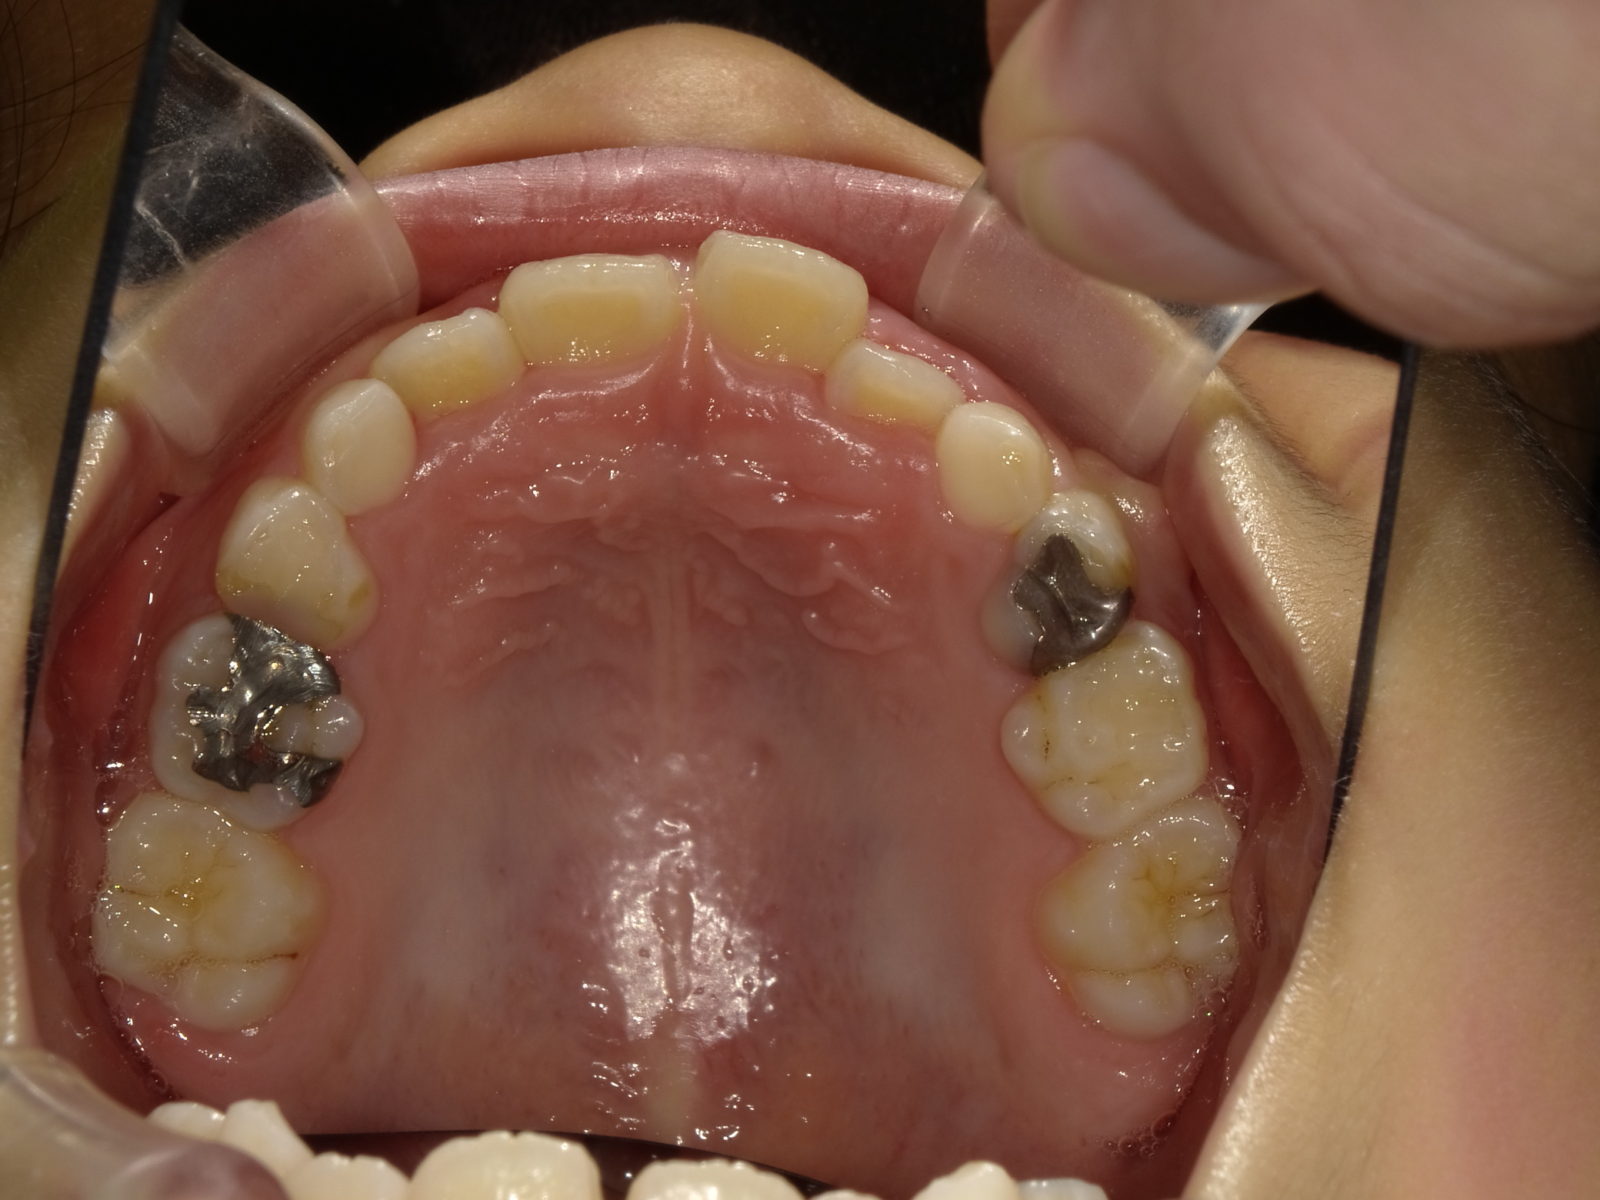

顎顔面矯正は、「急速拡大装置」を利用し、正中口蓋縫合と呼ばれる部分を広げ、顎骨の成長を促していきます。下の画像のように「ねじ」を回すことで装置を徐々に広げていきます。